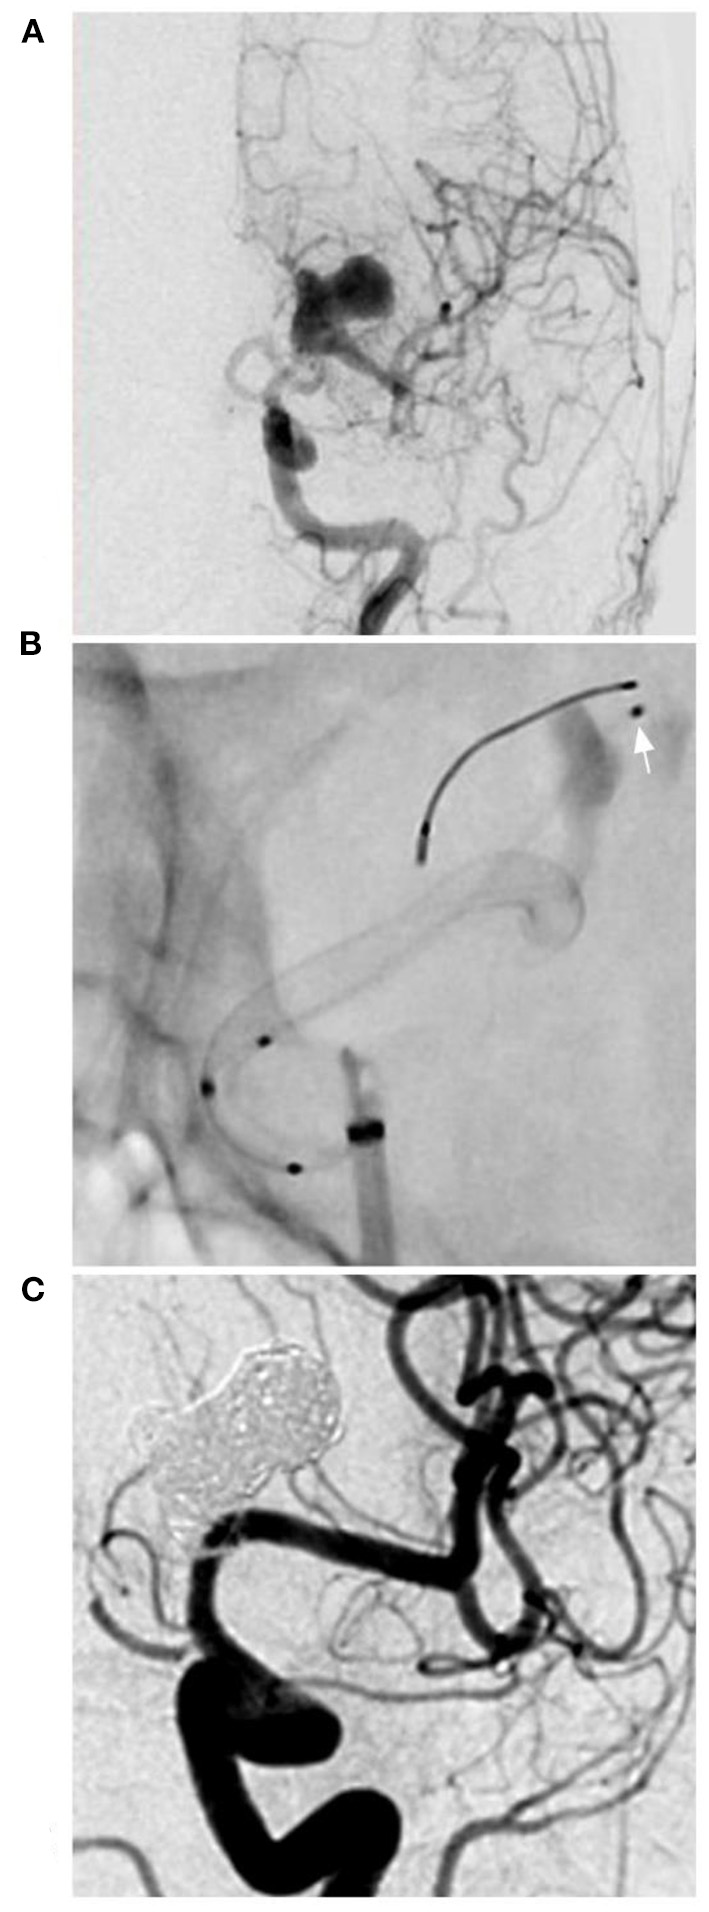

All patients were available at the clinical follow-up, and the clinical and imaging follow-up ranged from 3 to 48 months (mean, 10.9 ± 11.4 months). All patients presented with a mRS score of 0 (100%). The degree of embolization was 100% occlusion in 22 aneurysms (95.6%, 22/23), and one aneurysm exhibited <90% occlusion (subtotal embolization with the prolongation of stasis in the arterial phase). Representative cases are shown in Figures 1, 2. Clinical data in this study are summarized in Table 1.

Figure 1

PED for an M1 complex aneurysm. (A) DSA of the anterior-posterior view of the ICA showing a complex lobulated aneurysm on the M1 segment of the middle cerebral artery. (B) X-ray film showing the deployment of the PED and the microcatheter (arrow) in the aneurysm to plan coiling. (C) Follow-up DSA showing complete aneurysm occlusion. DSA, digital subtraction angiography; ICA, internal carotid artery; PED, pipeline endovascular device.

Intracranial aneurysms beyond the circle of Willis are often dissecting and long but not large. Delayed rupture was uncommon after FD deployment, so the aim of coiling assistance was not to reduce the rupture risk; coiling may increase the degree of aneurysm occlusion. The coiling assistance during FD deployment was the same as that during conventional stent-assisted coiling. For instance, in the case shown in Figure 1, follow-up showed excellent occlusion after coiling assistance. However, coiling assistance is selectively applied for intracranial aneurysms beyond the circle of Willis, because in these aneurysms, the blood flow is not abundant, and FDs alone may be sufficient in most of these cases. In our study, 7 aneurysms were treated with coils in the aneurysms, including 4 recurrent aneurysms and 3 new cases requiring coiling assistance during PED deployment, and complete occlusion was obtained. Coiling assistance was feasible, but whether there is a difference between aneurysms with or without previously coiling requires further study. In our study, due to the small number of cases, it was difficult to identify such a difference. However, PED deployment was safe and effective.